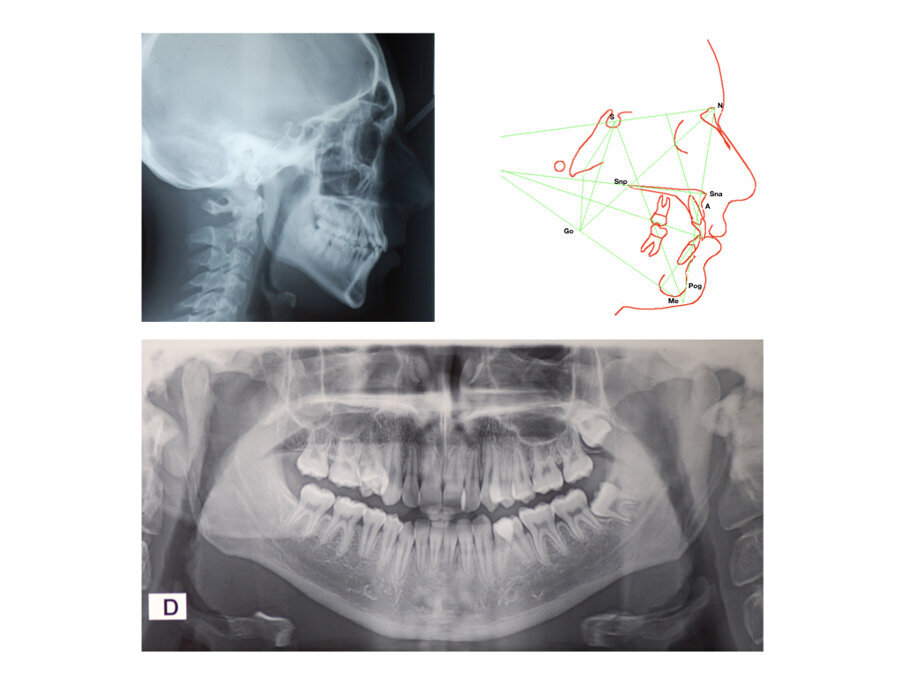

Analisi Radiografica

La radiografia panoramica (Fig. 2) mostra una sovrapposizione dentale sul primo quadrante tra 1.4 e 1.5 e sul terzo quadrante a livello coronale tra 3.4 e 3.5. I condili mandibolari sono simmetrici e non sono visibili patologie mascellari sinusali. Tutti i denti permanenti sono visibili. Vi è l’agenesia del 4.8 ed 1.8 mentre vi è la mancata eruzione del 3.8 ed 1.8. Non vi sono dilacerazioni radicolari, si nota un riassorbimento radicolare con una mancata formazione dell’apice radicolare del 4.5, 3.5. La radiografia laterale del cranio (Fig. 2) mostra le vie aeree superiori libere. L’indice di maturazione delle vertebre cervicali (CVMS) è di grado 6. L’analisi cefalometrica iniziale rivela una classe II sagittale mandibolare a causa di una mandibola retrognatica (SNPog = 72,2°), un tendenza mandibolare di iperdivergenza, ed un angolo interincisale ridotto. L’OJ e l’OB è nella norma.